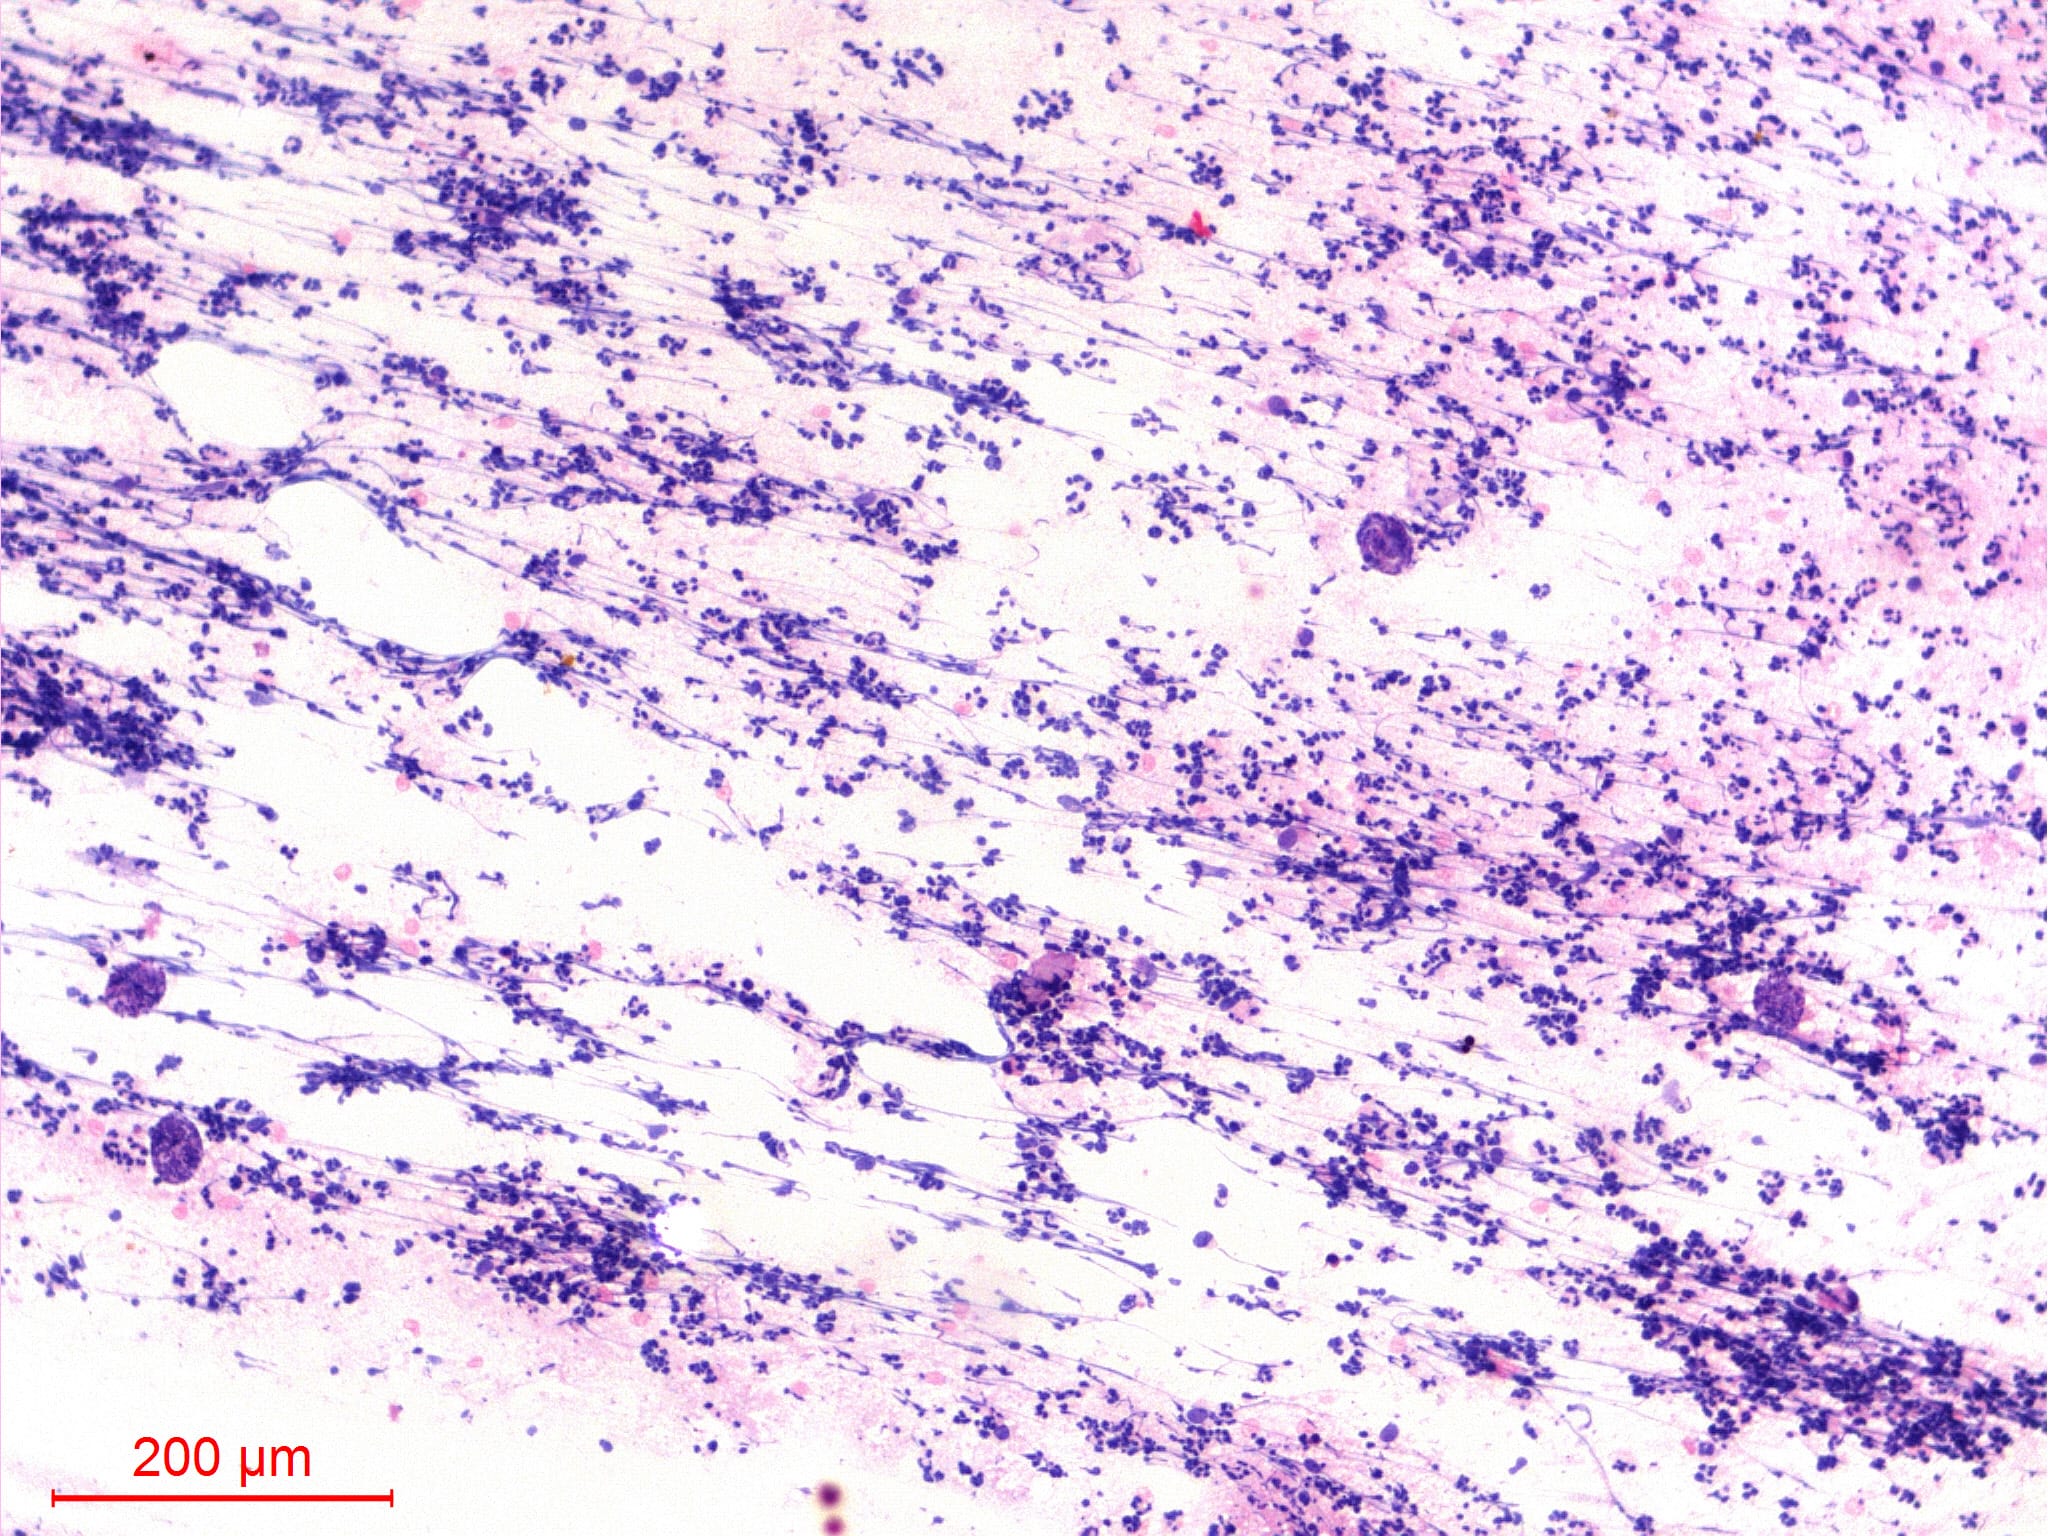

Microscopic (histologic) description

Microscopic (histologic) images

Contributed by Sajna V.M. Kutty, M.D.

- Filariasis is due to infection by threadlike nematodes of the family Filarioidea

- Filarial infection can cause lymphedema of the limbs (elephantiasis), genital disease (hydrocele, chylocele and swelling of the scrotum and penis) and recurrent painful acute attacks (WHO: Lymphatic filariasis [Accessed 29 March 2021])

- Wuchereria bancrofti accounts for up to 90% of cases

- Diagnosis is typically made by identifying microfilariae in peripheral blood smears

- Rarely, microfilariae are coincidentally detected in FNAC in association with various inflammatory and neoplastic lesions

- Wuchereria bancrofti can be identified by its sheath and multiple, coarse, discrete nuclei extending from head to tail except in the small terminal portion of the caudal end

- Wuchereria bancrofti accounts for up to 90% of cases

- Adult worms lodge in the lymphatics, where females release larvae (microfilaria) which periodically circulate in the blood and are occasionally ingested by feeding mosquitoes

Microscopic (histologic) description

- Wuchereria bancrofti can be identified by its sheath and multiple, coarse, discrete nuclei extending from head to tail except in the small terminal portion of the caudal end

Microscopic (histologic) images

Contributed by Sajna V.M. Kutty, M.D.